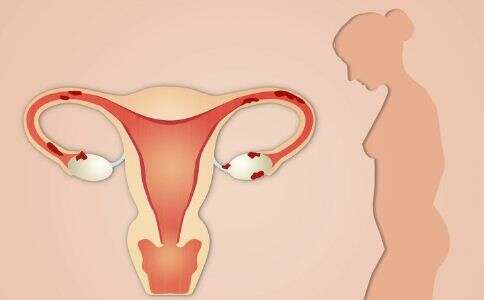

输卵管是女性生殖系统中的重要组成部分,它把卵子从卵巢输送到子宫,以便受精卵的发育。输卵管受精问题是不少女性绝经后受孕难的主要原因,所以保持输卵管的健康是很重

输卵管堵塞不孕或久备难孕,是可以考虑试管婴儿助孕的。 输卵管堵塞初期有什么症状? 1、明显小腹疼痛 由于输卵管堵塞炎症有可能造成盆腔炎症,有可能会出现

输卵管堵塞是一种妨碍受孕的常见病因,一旦发现输卵管堵塞,患者可以选择手术治疗或复通治疗,但如果治疗失败,有没有其他受孕方式呢?答案是肯定的,输卵管堵塞也可以